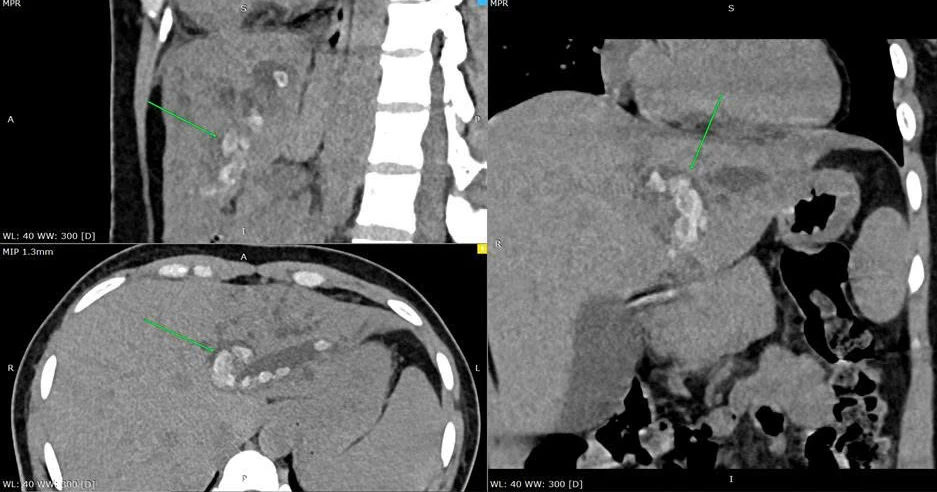

Bệnh nhân là chị T.T.K (42 tuổi, quê Cần Thơ) nhập viện trong tình trạng đau bụng vùng thượng vị, nôn ói, sốt lạnh run kéo dài 2 ngày. Qua thăm khám và các xét nghiệm cận lâm sàng, bác sĩ chẩn đoán bệnh nhân bị nhiễm trùng đường mật do sỏi đường mật nhánh gan trái.

Vị trí sỏi đường mật. Ảnh: BVCC

Bác sĩ chuyên khoa I Hồ Nam Anh, Khoa Ngoại tổng hợp, Bệnh viện TP Thủ Đức, cho biết đối với trường hợp này, phẫu thuật cắt gan là phương pháp điều trị phù hợp nhất do sỏi khu trú ở một thùy gan và gây nhiễm trùng tái phát.

“Phương pháp này có ưu điểm là loại bỏ triệt để ổ sỏi đường mật, giảm nguy cơ tái phát và giải quyết được các tổn thương kèm theo” - bác sĩ Nam Anh nói.